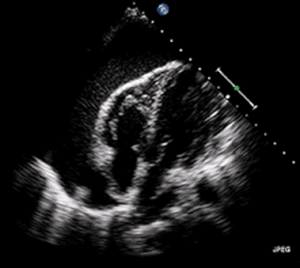

| A 2D transthoracic echocardiogram of a massive pericardial effusion. The "swinging" heart | |